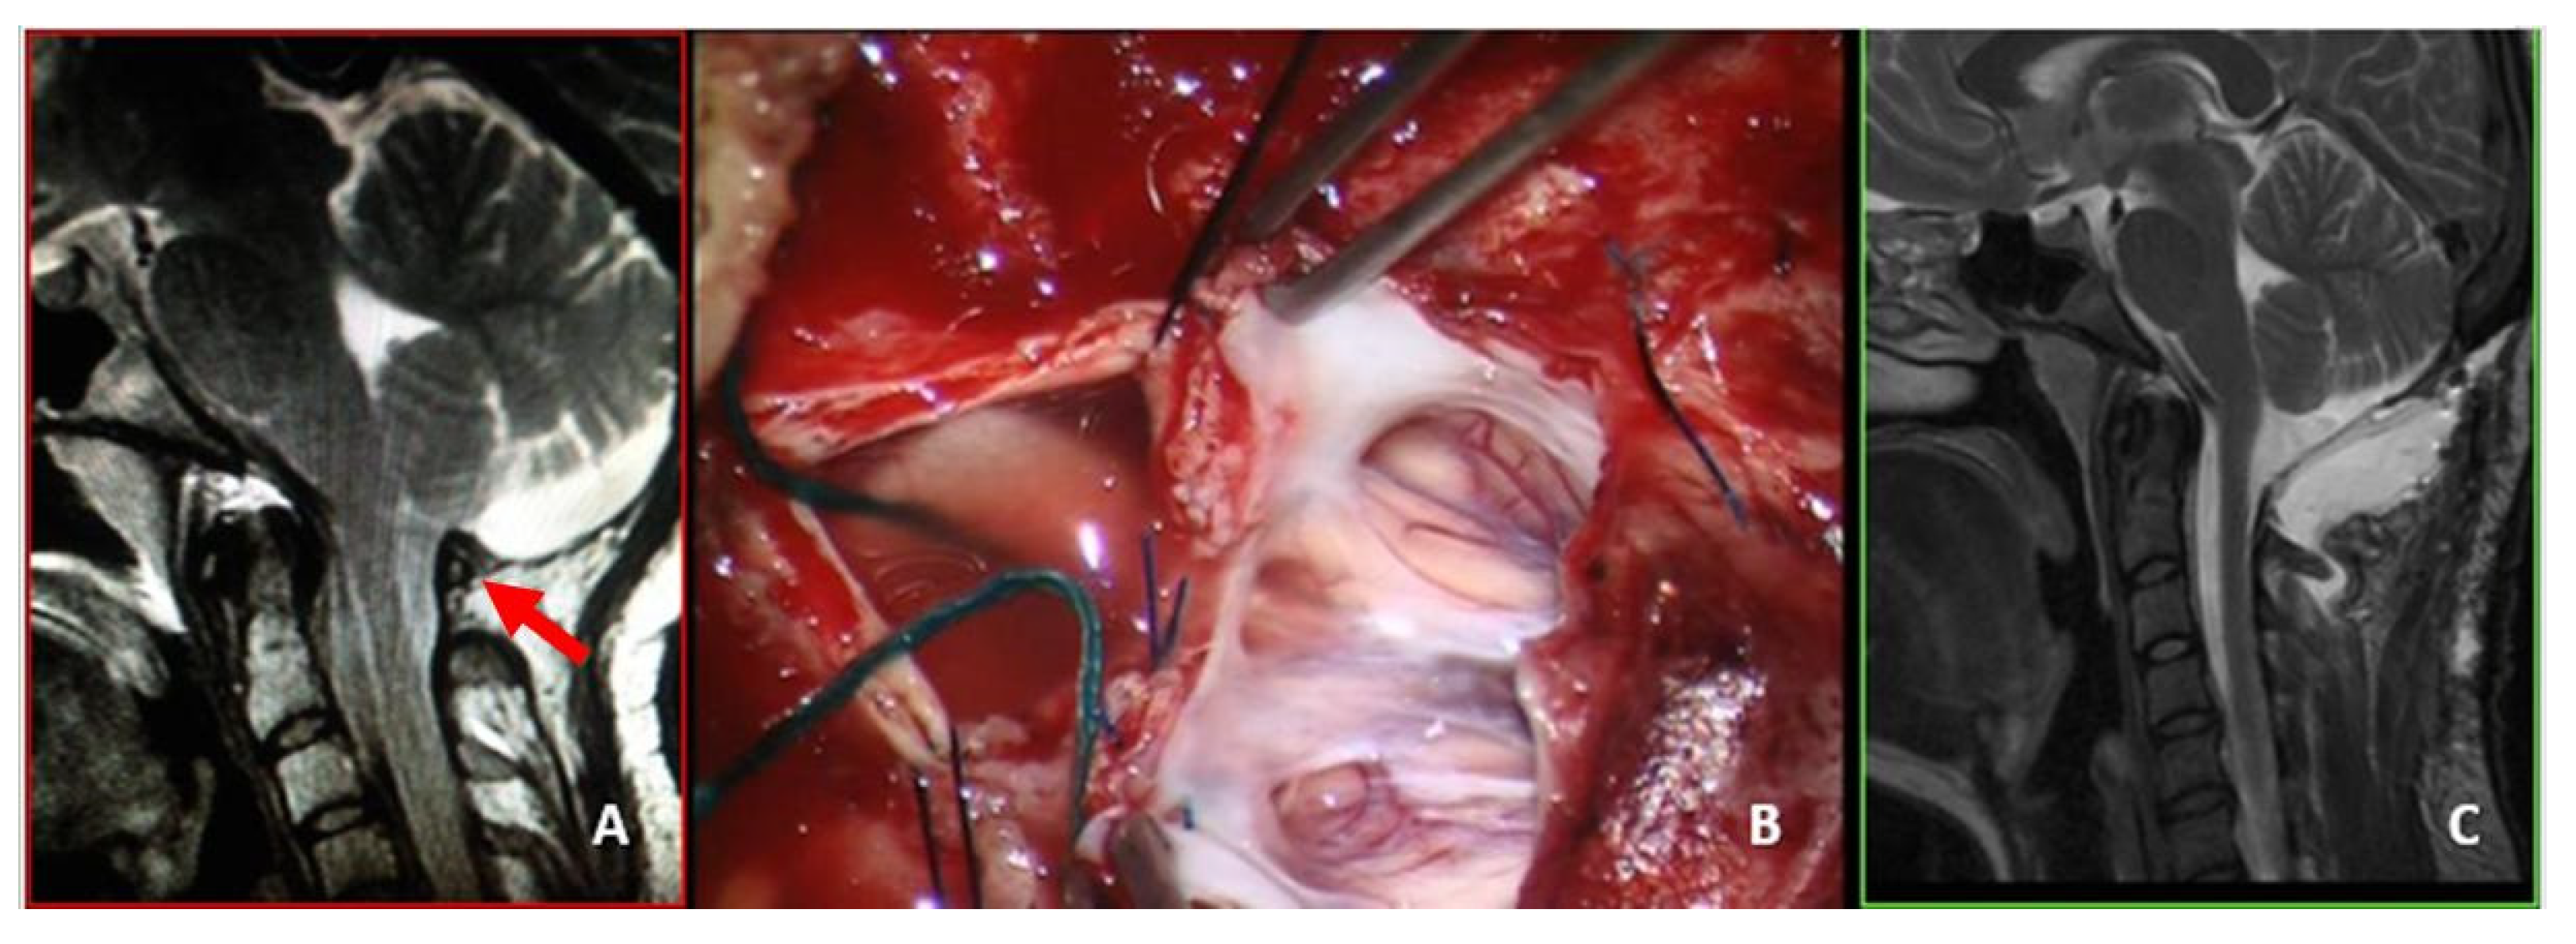

This group consisted of 11 adult patients. Six patients showed transitory improvement followed by symptom recurrence, whereas the remaining five received no benefit at all. This group included patients who had undergone different treatments. There were three patients with FMD-WDA who were reoperated for dural augmentation. Three other patients had been managed by FMD + DA, leaving C1 intact, which maintained a certain level of compression. The reoperation consisted of laminectomy and intradural exploration (Figure 4).

Two other patients presented with worsening headache and rigor nucalis following a transitory improvement. These patients had undergone FMD + DA with biological meningeal grafts. MRI scans showed meningeal enhancement and reduced subarachnoid space with scarce CSF-flow in both cases. The reoperation consisted of graft substitution and arachnoid dissection (Figure 5).

One of the three patients with C1 intact also had very tight adhesions between the cerebellar cortex and the overlying biologic dural graft, which had to be meticulously detached and replaced using an inert dural substitute of polyurethane (Figure 5). These three patients experienced partial improvement, but their QOL remained unchanged (final CCOS = 12 in one case and 10 in two cases).

Figure 4. This 64-year-old woman had been treated with osteodural decompression, leaving C1 intact. One year later, she was referred to us for severe nocturnal breathing disturbances and mild quadriparesis. (A) Preoperative MRI, T2-weight, sagittal view, showing a small craniectomy with C1 still maintaining a significant obliteration of the arachnoid space (red arrow). A wide syringomyelia was evident. You will notice a marked skin retraction over the craniectomy (yellow arrow). (B) Intraoperative picture showing an “arc” incision and the skin retraction. The reoperation consisted of C1 laminectomy, tonsillectomy, and dural sac augmentation. (C) Postoperative MRI, T2-weight, sagittal view showing a relatively large subarachnoid space and initial syrinx shrinkage. There was mild local cerebellar edema owing to the tonsillectomy. An asymptomatic pseudomeningocele was also evident, which resolved spontaneously within a couple of weeks. Since the first postoperative period, breathing disturbances have significantly improved, whereas quadriparesis improvement has been slower. The final CCOS score was 10.

Figure 5. This 29-year-old woman had undergone osteodural decompression without laminectomy. One year later, she was admitted to our department with an untreatable persistent hiccup responsible for difficult alimentation, invalidating headache, dizziness, tinnitus, fever, rigor nucalis, and diffuse asthenia. An infection was suspected, but was ruled out. (A) Preoperative MRI, T2-weight, sagittal view showing a relatively wide craniectomy with C1 (red arrow) still compressing the arachnoid space, and a scarce presence of CSF around the CM-1. She underwent laminectomy and dural sac augmentation. (B) Intraoperative picture depicting a diffuse, tight adherence between the dural graft and the parenchyma. To replace the graft, a meticulous dissection was necessary. Finally, the dural sac was repaired with a synthetic graft. (C) Postoperative MRI, T2-weight, sagittal view showing a well-bathed CM-1. An asymptomatic pseudomeningocele was detected. This remained completely asymptomatic, even though it was still evident (but reduced) 6 months later. One year after the reoperation, the patient reported sporadic headache bouts, but had no other symptoms. The final CCOS score was 13.